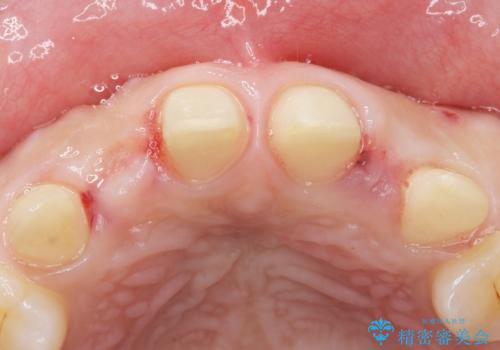

矯正以外の治療法で早く治したいとのご希望により、上顎両側犬歯を抜去しオールセラミックのブリッジによる補綴治療を行いました。

- ¥660,000 (仮歯×6本、クラウン×6本)費用は治療当時の料金となります